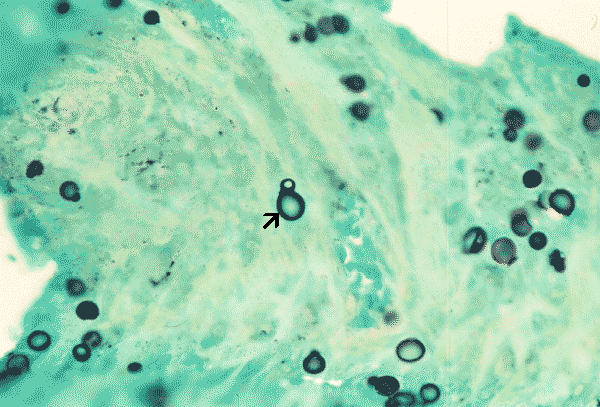

Blastomyces dermatidis, GMS stain

Note the characteristic broad base budding (arrow).